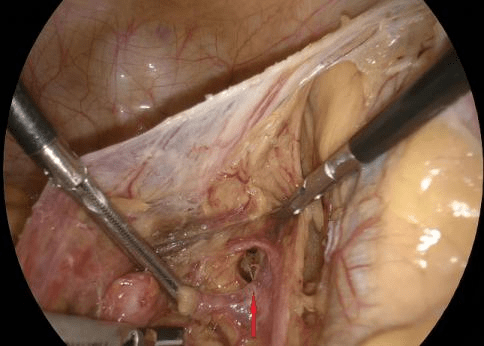

术中 , 该院疝腹壁外科专家李宝山和肛肠外科专家孙轶凭借精湛的微创手术技术 , 应用4K超高清腹腔镜系统顺利完成一系列复杂操作 , 成功对老人的盆腔骶前侧方组织进行分离 , 嵌顿输尿管松解还纳 , 以及缺损缝合 。 为防止再次发生同样病情 , 专家团队还用生物补片对老人的坐骨大孔进行了修补 。

(上图红色箭头所指是坐骨大孔术前和修补后 )